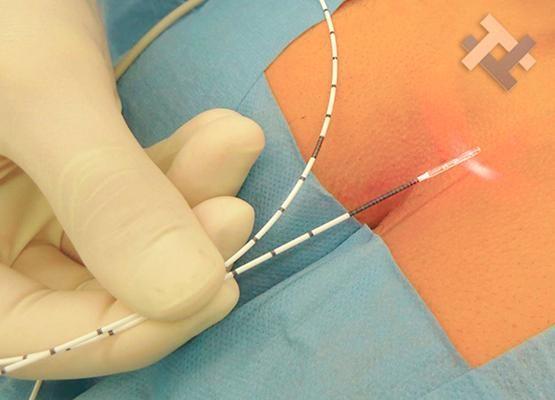

Χειρουργική laser σύγχρονων κυκλικών ινώνΘεραπεία αιμορροϊδων με laser (LHP) Αφαίρεση αιμορροΐδων με υπερήχους (HALL-RAR) Xωρίς χειρουργείο με ελαστικούς δακτυλίους (Τεχνική BARON-RBL)

Χειρουργική laser σύγχρονων κυκλικών ινών

Θεραπεία αιμορροϊδων με laser (LHP)

Ο Γενικός Χειρουργός Λιάγκος Γεώργιος MD PhD εκτελεί τις επεμβάσεις Λαπαροσκοπικά, Ενδοσκοπικά, Ανοιχτά Ελάχιστα Επεμβατικά και με Laser. Η θεραπεία εξατομικεύεται σε κάθε ασθενή ανάλογα με τις ανάγκες του. Αναλαμβάνει περιπτώσεις όπως κήλες και κοιλιοκήλες (αντιμετώπιση βουβωνοκήλης, αντιμετώπιση ομφαλοκήλης, θεραπεία επιγαστρικής κήλης, κήλη των αθλητών (Σύνδρομο κοιλιακών προσαγωγών), αντιμετώπιση μετεγχειρητικής κήλης, θεραπεία Μηροκήλης), πέτρες στη χοληδόχο κύστη, λαπαροσκοπική χολοκυστεκτομή, αντιμετώπιση Κύστη Κόκκυγος με λέιζερ (laser), παθήσεις πρωκτού, χειρουργική laser σύγχρονων κυκλικών ινών (αιμορροΐδες αντιμετώπιση, θεραπεία αιμορροϊδων με laser (LHP), αφαίρεση αιμορροΐδων με υπερήχους (HALL-RAR), χωρίς Χειρουργείο με ελαστικούς δακτυλίους (Τεχνική BARON-RBL), θεραπεία ραγάδας πρωκτού (Ραγάδα δακτυλίου), θεραπεία περιεδρικού συριγγίου, θεραπεία περιεδρικού αποστήματος, κονδυλώματα πρωκτού Θεραπεία, δερματικό ράκος (Skin tag) εκτομή, αντιμετώπιση Kνησμού, καρκίνος πρωκτού θεραπεία), παθήσεις Δέρματος, χειρουργική με laser CO2, αφαίρεση μορφωμάτων δέρματος - βιοψίες, αφαίρεση ελιάς (Σπίλου), σμηγματογόνος κύστης θεραπεία, αφαίρεση λιπώματος, είσφρυση όνυχος χειρουργείο, καρκίνος δέρματος θεραπεία, οξεία σκωληκοειδίτιδα, παθήσεις Λεπτού και Παχέος Εντέρου, ειλεός λεπτού εντέρου, εκκολπωμάτωση (Εκκολπωματίτιδα) σιγμοειδούς, καρκίνος παχέος εντέου, κολοστομίες, port χημειοθεραπείας κ.α. εξυπηρετώντας Παγκράτι και γύρω περιοχές.